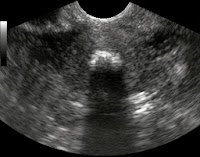

Endometrial ossifikasyon uterus içerisinde endometriumda kemiksi yapı izlenmesidir, çok nadir görülen bir patolojidir. Genellikle infertilite veya menoraji nedeniyle yapılan incelemeler sırasında teşhis konur. Endometrial biyopsi veya histerektomi materyalinin histopatolojik incelemesinde tanı konulabilir. Endometrial kavitedeki ossifikasyon bazen ultrasonografide ve makroskopik incelemede görülebilirken bazen sadece mikroskopik histopatolojik incelemede farkedilebilir.

Ultrasonografide RİA benzeri görüntü oluşturabilir (kaynak). Endometrial tüberküloz da kavitede kalsifikasyona ve infertiliteye neden olabilmesi ile endometrial ossifikasyonla benzerlik gösterebilmektedir. Abortus sonrası uterin kavitede kalan fetusa ait bazı parçalar da benzerlik gösterebilmesi açısından anamnezde abortus sorgulanmalıdır.